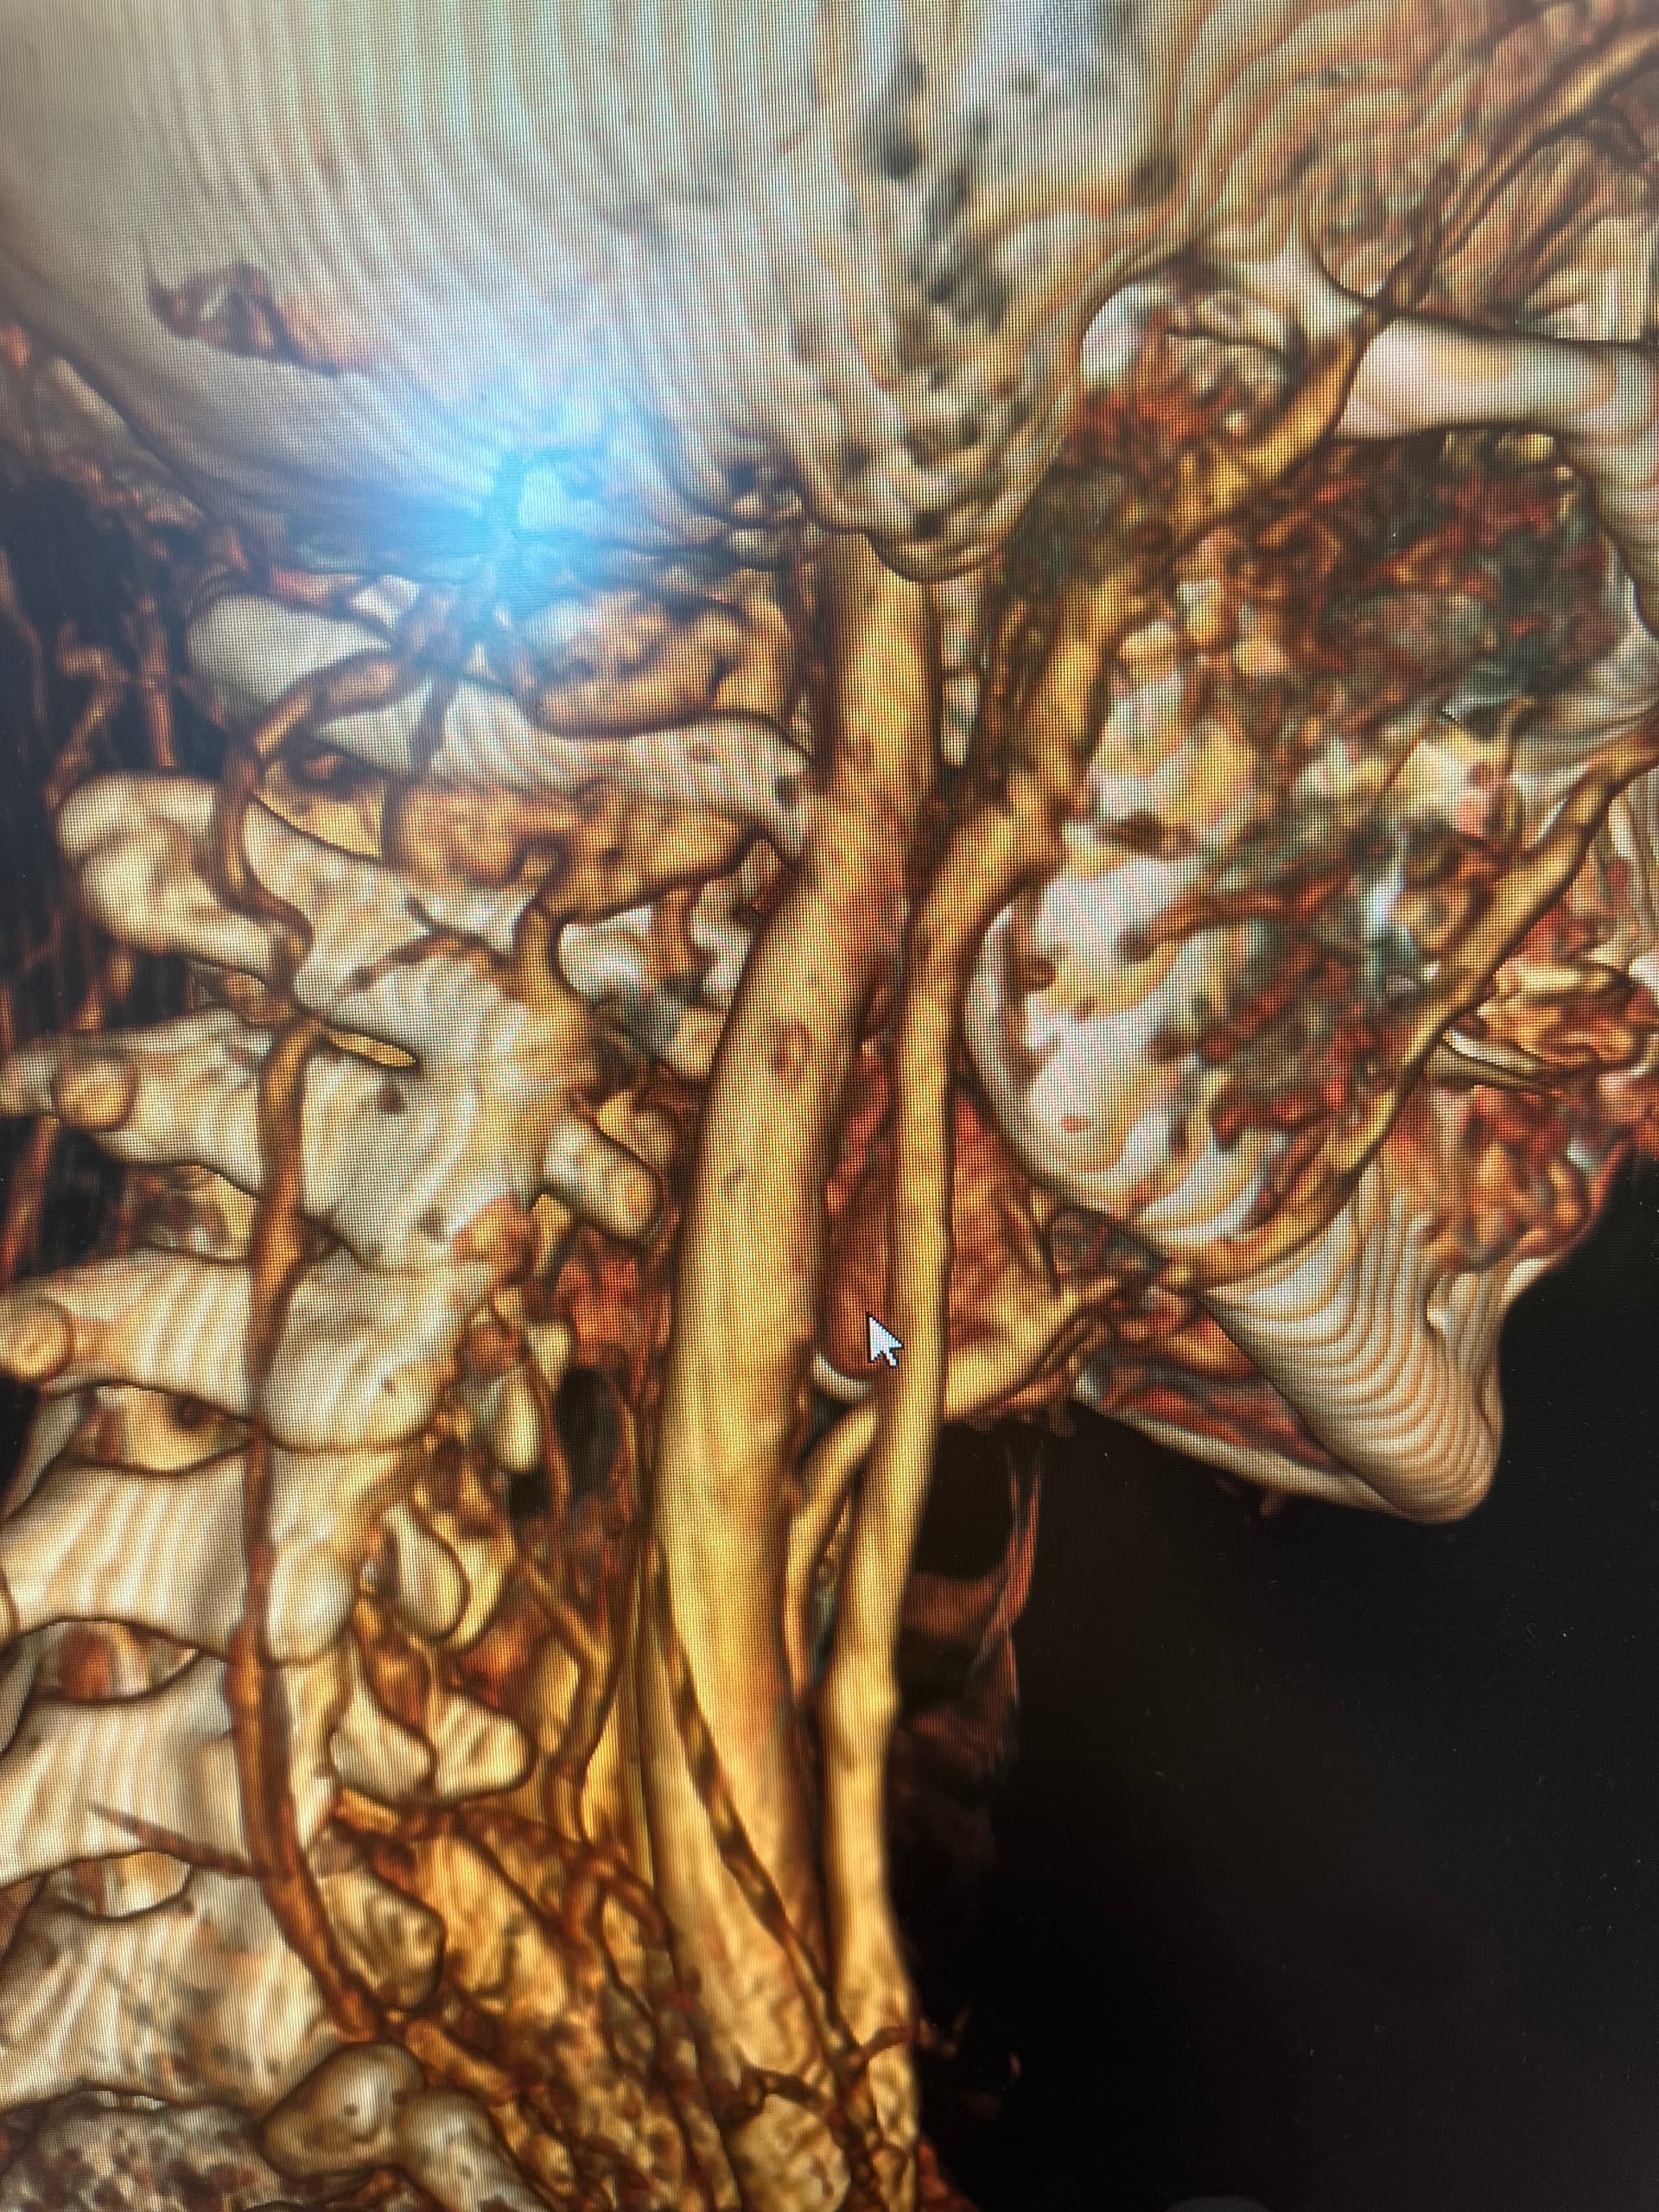

Might want to check out left styloid process and ligament also. Can see it on the 3D but not all of it due to blood vessels. Might be contributing to the hyoid injury/problem if ligament is calcified.

Good observation, @Rex!

So frustrating that you were doing well! The hyoid bone processes do look quite long & very close to your vertebrae, as the others have said, so worth looking in to if you can…